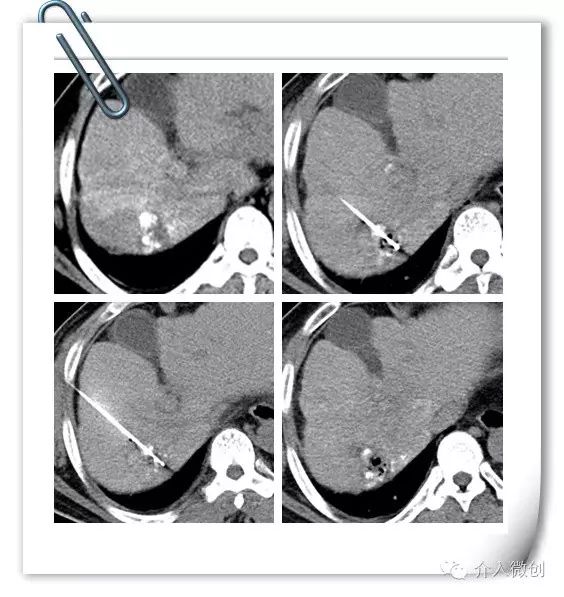

老年男性,诊断为原发性肝癌并门静脉癌栓形成,前期行肝动脉栓塞+放射性粒子植入治疗控制肝内病灶及门静脉分支癌栓。

术前MRI显示门静脉系统广泛癌栓形成,食管胃静脉曲张明显

近期出现食管胃静脉曲张破裂出血,予以行TIPS分流减低门静脉压力,联合放射性条植入至门静脉内行癌栓近距离照射治疗,到达标本兼治。